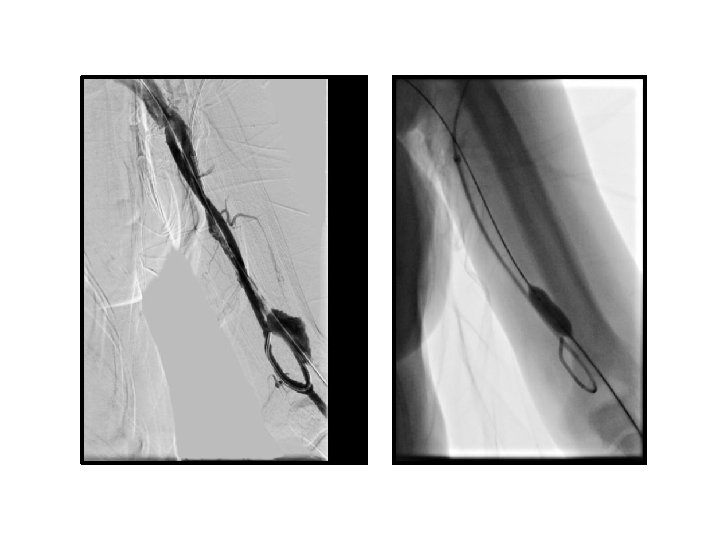

fibrin kılıf • Tedavi seçenekleri – Fibrinolitik ajan (infüzyon / lock tdv) – Mekanik olarak fibrini temizlemek • Kılıf sıyırma (snare) • Balon dilatasyonu – Farklı bir akses oluşturma

PTA sırasında oluşan venöz komplikasyonlar

• venöz rüptür (%2, 1 - 20) • akut / gecikmiş rüptür • minimal ekstravazasyon ve küçük hematom → damar duvar bütünlüğünde belirgin bozulma ve masif hematom • venöz diseksiyon

venöz rüptür • • • Manuel kompresyon Balon tamponat Stent yerleştirme Embolizasyon Cerrahi ligasyon

venöz rüptür